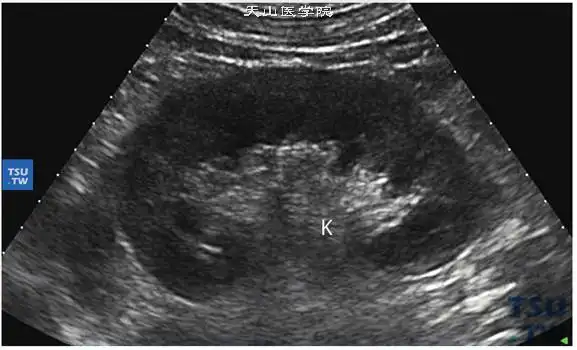

正常肾超声图像: 肾脏自外向内依次为肾被膜轮廓线,中等回声略偏低的